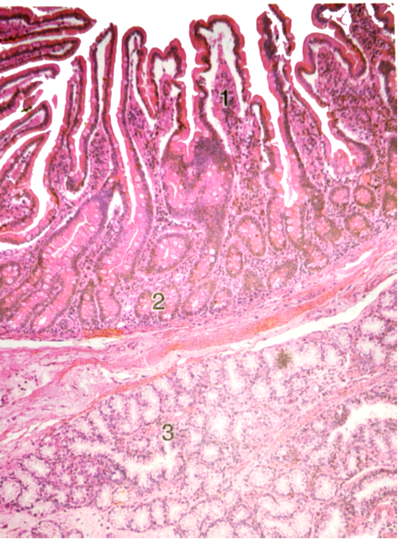

1.空肠或回肠(横切)切片(HE染色)

(1)肉眼观察:管腔面有凹凸不平的皱壁,粘膜染成紫蓝色,皱壁表面可见细小突起为小肠绒毛;外面一圈染成红色为肌层。

(2)低倍镜观察:粘膜表面有许多呈叶状突起的小肠绒毛,固有层内含有小肠腺。粘膜下层为疏松结缔组织,含有较多血管和淋巴管。肌层由内环行和外纵行两层平滑肌组成。外膜为浆膜。

(3)高倍镜观察:绒毛的浅层为单层柱状上皮,其间有杯状细胞。绒毛中轴的固有层结缔组织内有1-2条毛细淋巴管,称中央乳糜管。